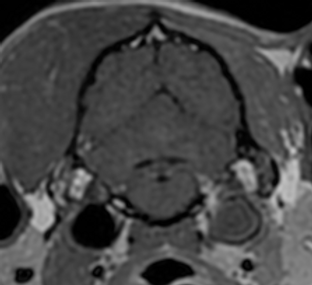

Jugular Foramen Syndrome: Concurrent Neurological Deficits, Advanced Imaging Findings, Underlying Diagnoses, and Outcomes in 14 Dogs (2016–2024)

Jugular foramen syndrome (JFS), dysfunction of cranial nerves (CNs) IX, X, and XI caused by lesions involving the jugular foramen (JF), is rarely reported in dogs.

Affected dogs were older (median age, 9.9 years; range, 7.9–14.5 years) and presented with chronic progressive clinical signs. Common presenting complaints included coughing (7/14), retching (6/14), head tilt (5/14), and laryngeal stridor (4/14). Neurologic abnormalities were noted in 11/14 dogs, with CN deficits (10/11), including unilateral laryngeal paralysis (5/10) and tongue atrophy (4/10), being the most common finding. Additional signs included head tilt (7/11) and postural reaction deficits (5/11). Intracranial lesions were identified in 10/14 dogs, with meningioma being the most frequent radiologic or histopathologic diagnosis. In dogs with extracranial lesions (4/14), thyroid carcinoma was common. Median survival time was 218 days (range, 16–477 days).